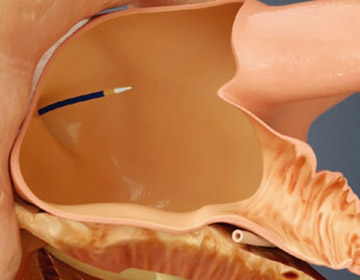

経皮的アプローチでガイドワイヤとダイレーターを右大腿静脈に挿入します。

X線と経食道心エコー(TEE)下で留置手技を実施します。経心房中隔穿刺システムを用いて心房中隔を通過します。

ガイドワイヤに沿って、アクセスシースを左上肺静脈または左心房内に進めます。次に、ピッグテールカテーテルに沿ってLAAの遠位側に誘導します。

WATCHMANを展開し、LAAに留置します。

WATCHMANを覆うように内皮化が進み、LAAが永久的に閉鎖されます。患者さんは、手技後約45日間は抗凝固薬の内服を継続します。経食道心エコーで閉鎖していることを確認します。